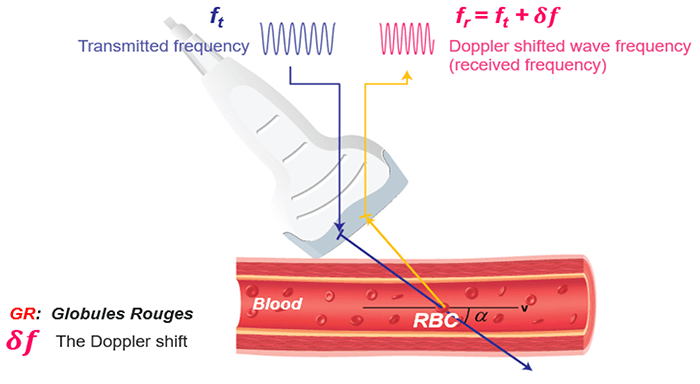

The same transducer acts as a transmitter and receiver in Doppler ultrasound applications. When using Doppler ultrasound technique to examine the blood flow in a vessel, the returning backscattered echoes from blood are detected by the transducer. These returning signals (Fr) are then processed to detect any frequency shifts by comparing these signals to the transmitted Doppler signals (Ft). The frequency shift detected will depend on two factors: the magnitude and the direction of the blood flow.

Doppler Equation

Let’s consider an example of a simple blood vessel. As shown in this figure, the transducer will first transmit a signal with frequency Ft, then this transmitted signal will reach a blood vessel. The transducer will receive the backscattered signals coming from the red blood cells at a frequency Fr.

The Doppler frequency shift (δf) is calculated by subtracting the transmitted signal Ft from the received signal Fr. As mentioned previously, this effect is used to study blood flow by measuring the frequency shift of echoes scattered by moving red blood cells.

Direction and Speed of Flow

Blood flow moving towards the probe produces positive Doppler shifted signal. On the other hand, blood flow moving away from the probe produces negative Doppler-shifted signals. The image on the top illustrates the change in the received backscattered signals and the resulting Doppler shifts for blood moving towards the transducer. In this image, the relative direction of the blood flow with respect to the Doppler beam is towards the transducer, blood flow moving towards the transducer produces received signals (Fr) which have a higher frequency than the transmitted beam (Ft).

The Doppler-shifted signal (δf) can be calculated by subtracting Ft from Fr and produces a positive Doppler shifted signal. The Doppler-shifted signal (δf) can be calculated by subtracting Ft from Fr and produces a positive Doppler shifted signal. Whereas, the second image illustrates blood flow which is moving away from the probe. Blood flow moving away from the transducer produces received signals (Fr) of lower frequency than the transmitted beam (Ft). This time the Doppler-shifted frequencies (Fr − Ft) produce a negative Doppler shifted signal. It is important to note that when there is no flow or movement detected, the transmitted frequency (Ft) is equal to the received frequency (Fr). Therefore Fr = Ft and The Doppler-shifted signal (δf) = Fr − Ft = 0, resulting in no Doppler-shifted signals.